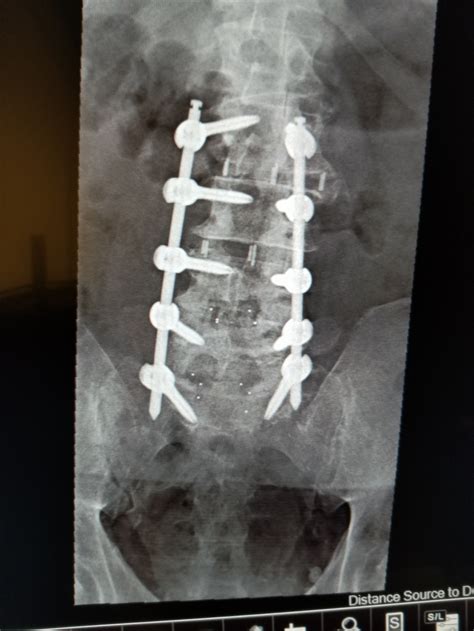

Undergoing back surgery is a significant life event that requires patience, discipline, and a thorough understanding of the healing process. Spinal fusion recovery is a journey that spans several months, as your body works to permanently connect two or more vertebrae to improve stability and alleviate chronic pain. While the prospect of surgery can be daunting, knowing exactly what to expect during the weeks and months following your operation can help you manage your expectations and ensure a safer, more successful outcome. By following medical guidance and adhering to physical therapy protocols, most patients find they can return to a meaningful, pain-free life.

The first few days following your procedure take place primarily in the hospital. Your medical team will focus on pain management and ensuring that you can perform basic movements safely. During this time, you will be encouraged to move around shortly after surgery—usually within 24 hours. Early mobilization is a cornerstone of effective spinal fusion recovery because it reduces the risk of blood clots and helps prevent stiffness.

The Roadmap of Spinal Fusion Recovery

Once you are discharged, the real work begins at home. It is essential to recognize that recovery is not linear; there will be days when you feel significantly better and others where fatigue or discomfort may linger. Understanding the timeline helps you pace yourself appropriately.